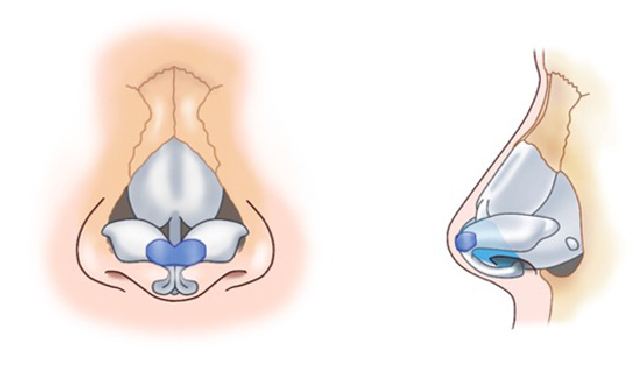

求める変化の大きさ、もともとの鼻の状態に応じ、採取部位を耳介軟骨、肋軟骨、あるいは鼻中隔軟骨から選択し、必要量のみ採取いたします。(上の図は耳介軟骨を採取して鼻中隔延長をするイメージ)

青い部分が移植した軟骨です。この軟骨の固定により、鼻の高さ、細さ、向きが大きく調節できます。